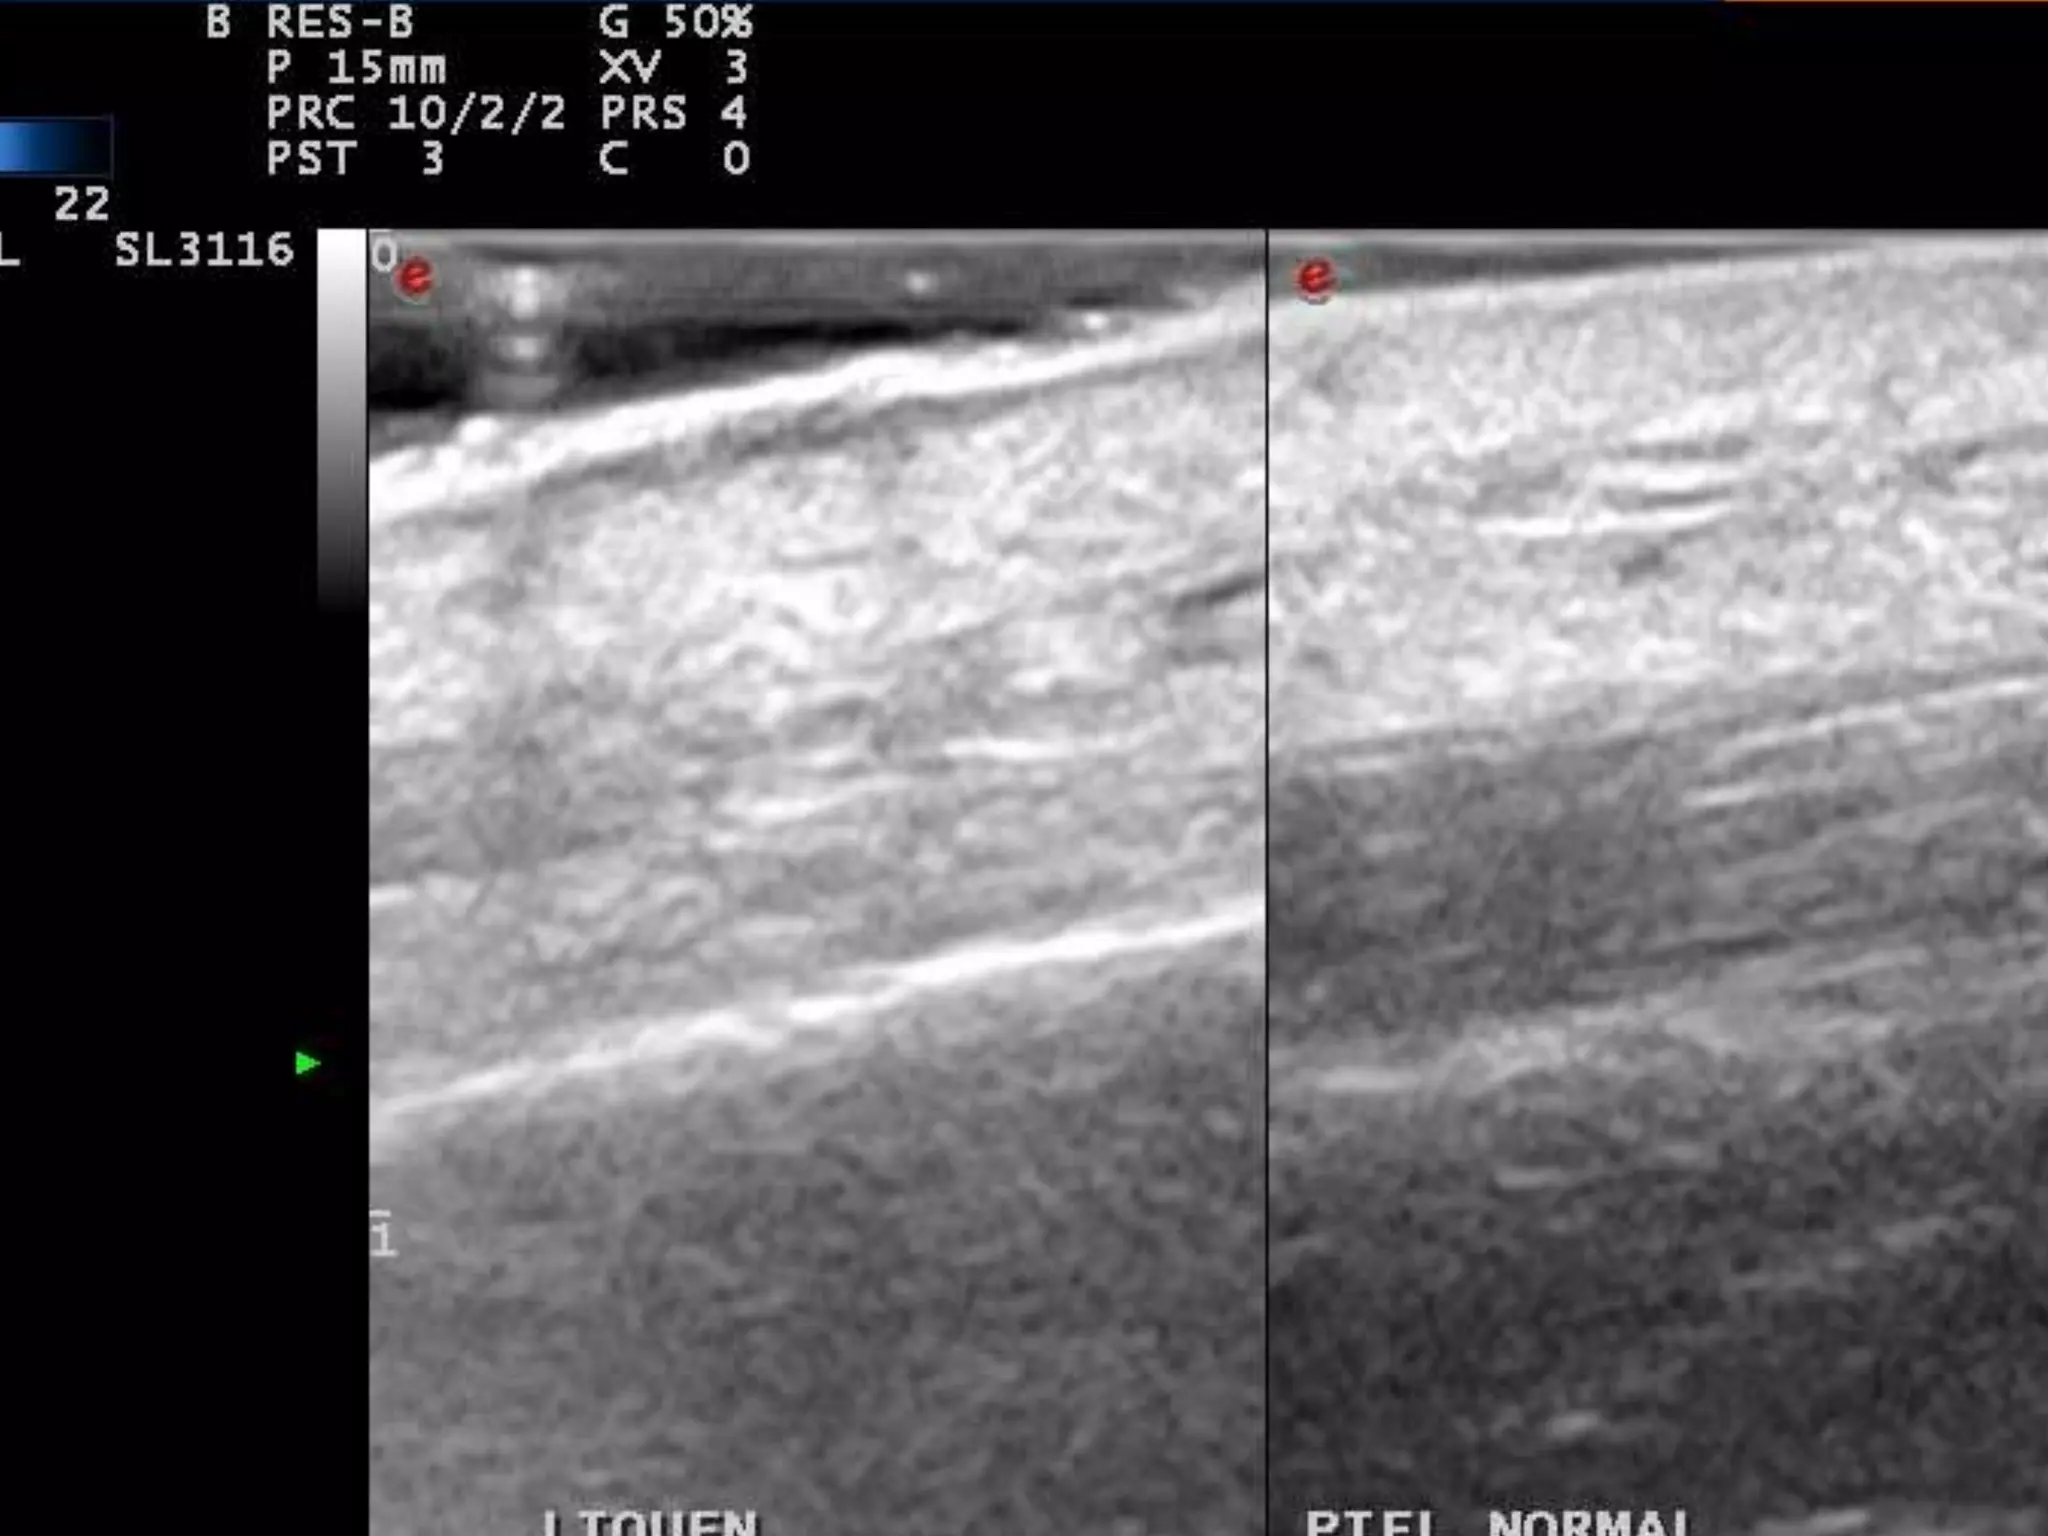

REGLAS “FÁCILES”

PARA DETECTAR INFLAMACION

1)La estructura inflamada se suele hacer

Hipoecoica = edema+células

2)El flujo Doppler Suele estar aumentado=

Aumento de flujo sanguíneo

3) COMPARAR, COMPARAR, COMPARAR